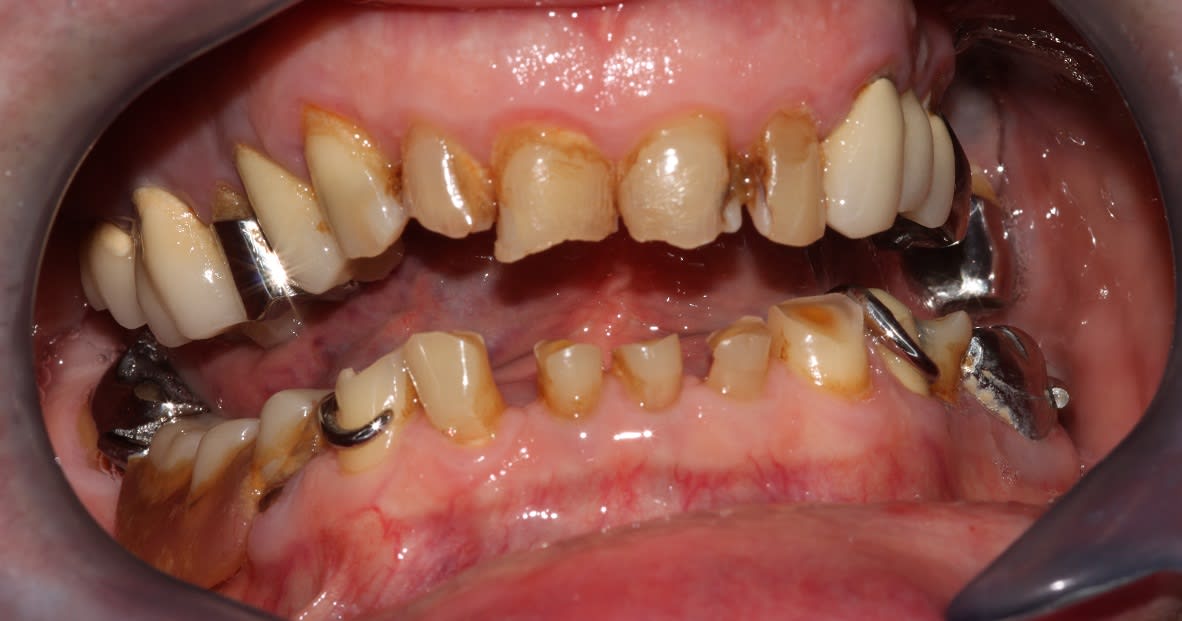

j'aime bien ton bricolage du stellite :-))

23 est une planche pourrie, l'endo de la 14 pose question.

on s’égare , on s égare . il faut d'abord connaitre la stratégie globale .

là tu as fait 1 prov 1ere generation en haut , ç est bien

apres tu feras un prov 1ere generation du bas , ce sera bien aussi .

ç est bien pcq quand tu prendras l'empreinte H+B de toutes les dents taillées , tu pourras les monter sur articu , et faire le wax . et ça ç est le top pcq tu feras le wax en fonction de tes criteres de taille donc de concervation des tissus dentaires .

je ne le redirais jamais assez : le wax doit etre fait sur les dents taillées . sinon ce n'est que de la peinture à la cire à bougie .( t'y rajoute une meche et ç est tres joli pour la veillée de noel ).